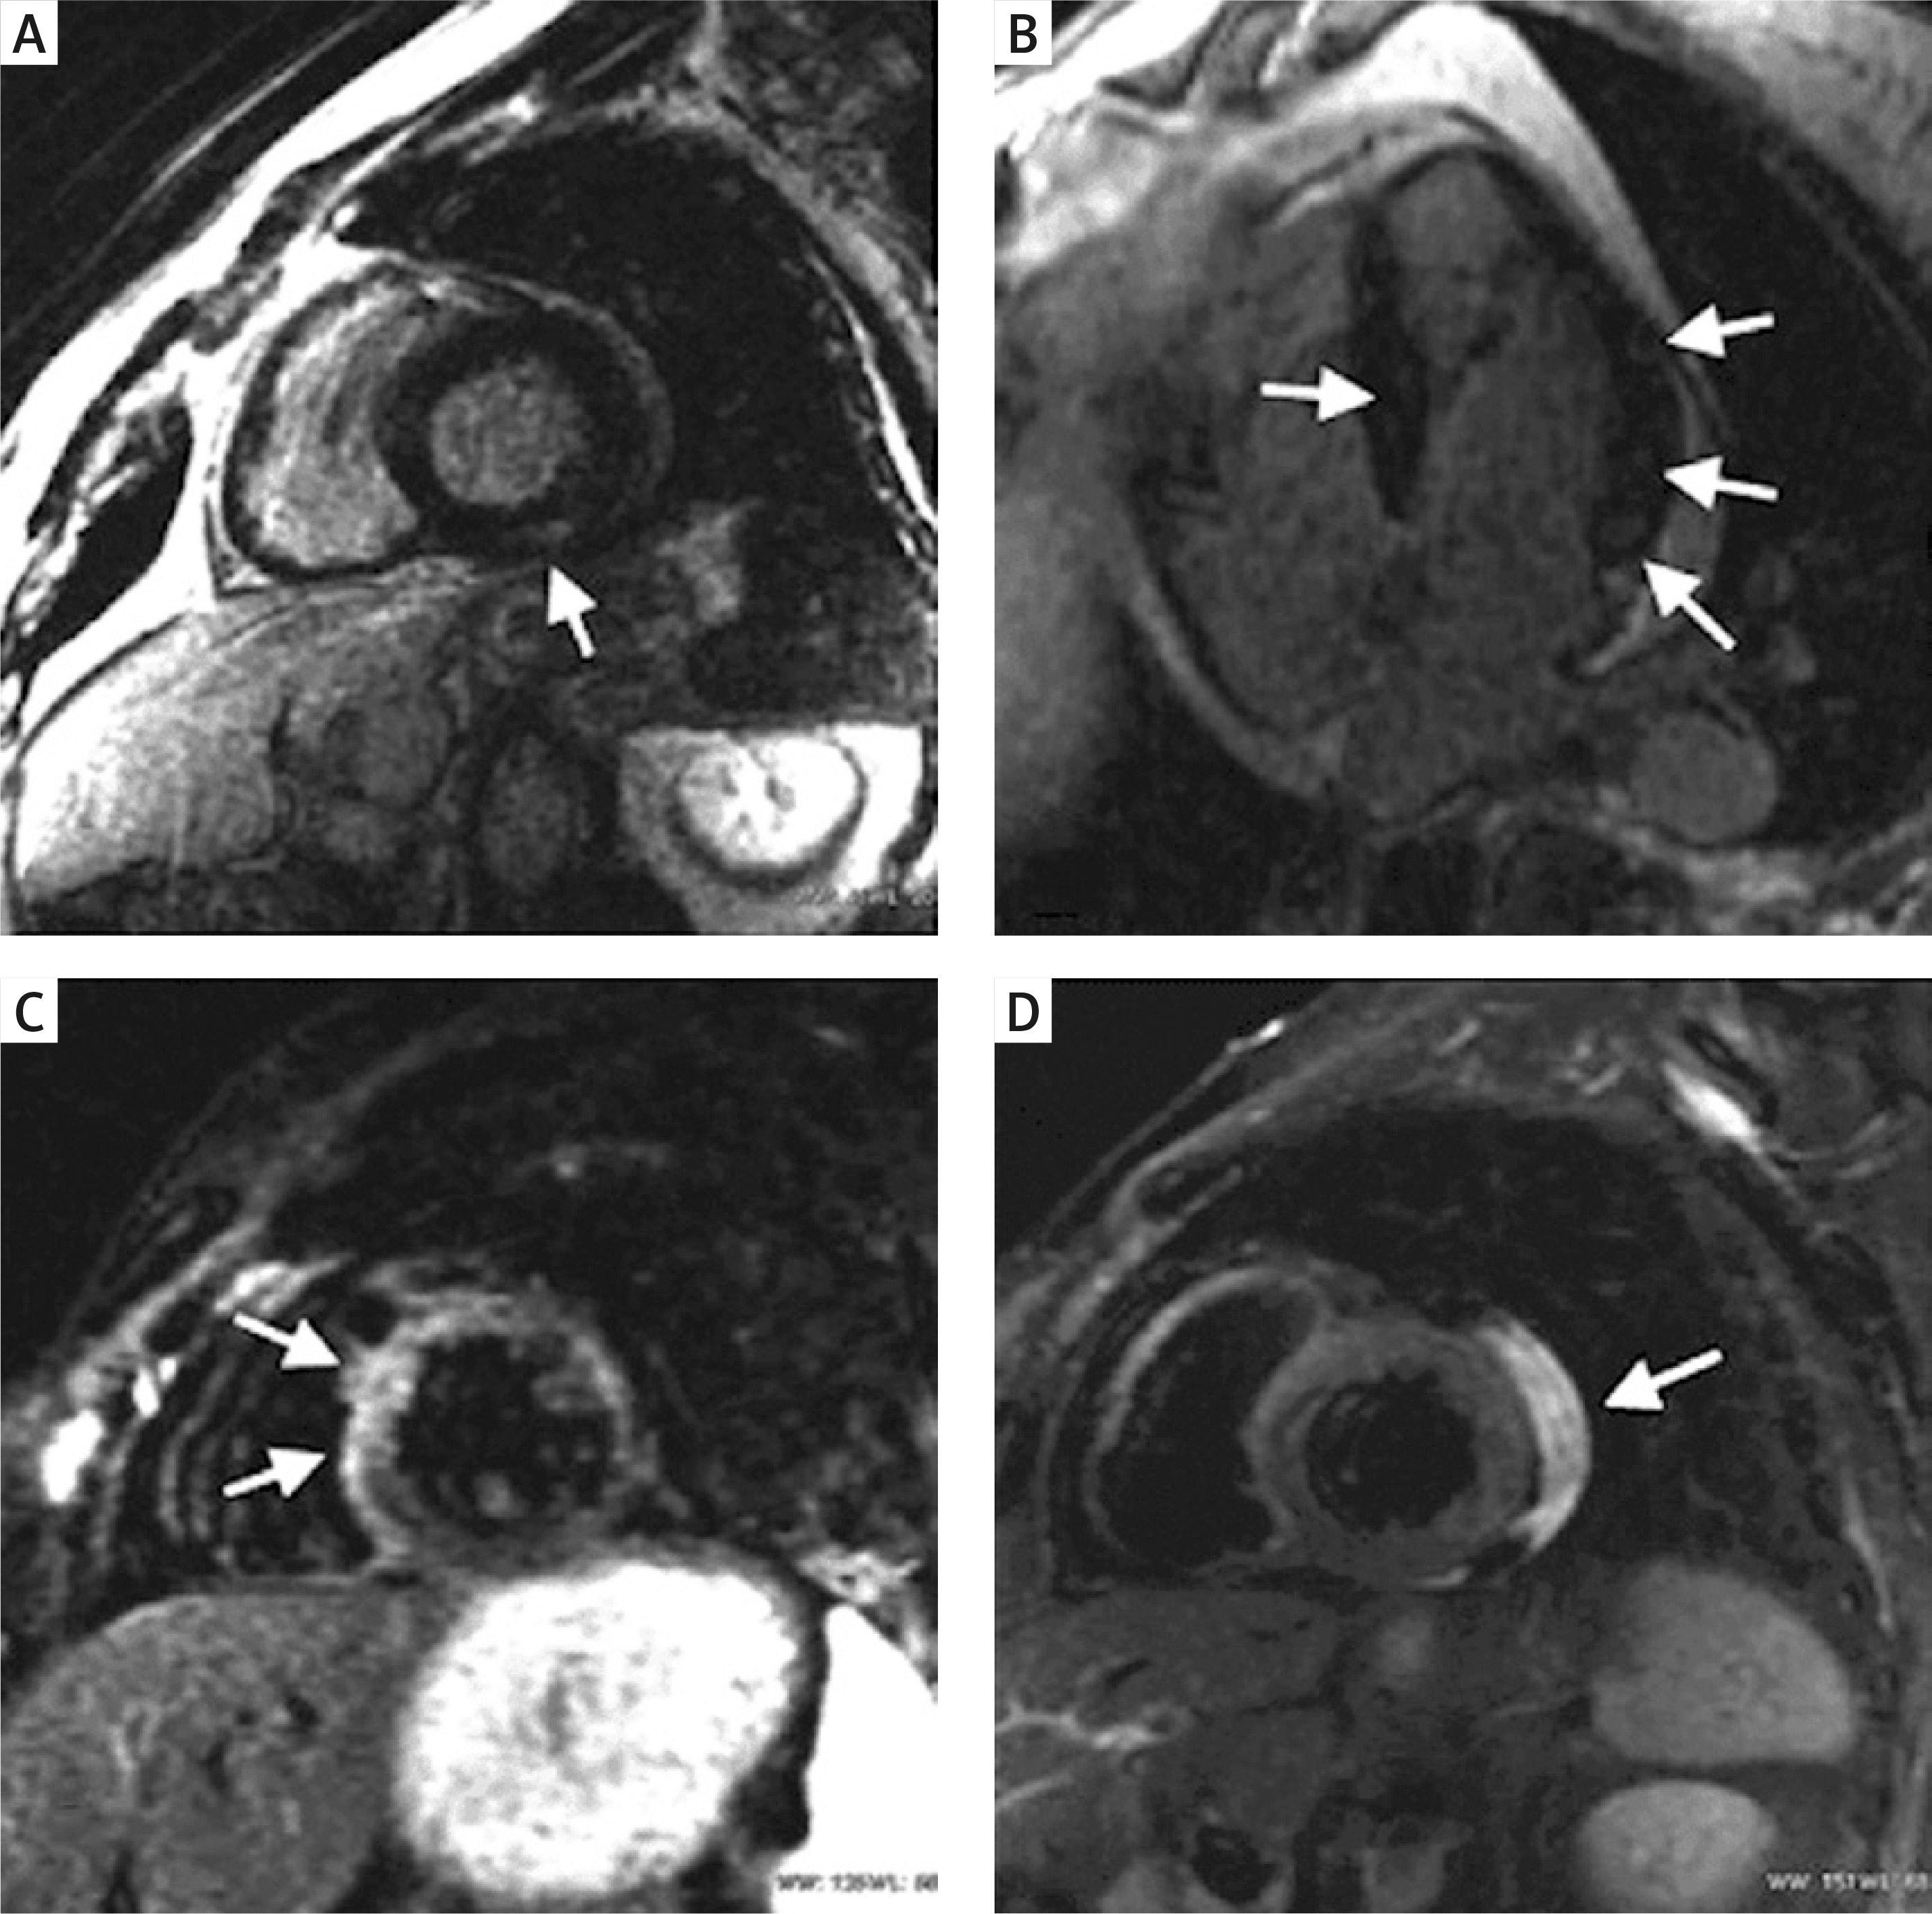

In assessing pericardial disease, a multimodality imaging approach is crucial. While two-dimensional echocardiography (2DE) can identify the existence of effusion or tamponade (evidenced by diastolic collapse of right-sided chambers, noticeable alterations in blood flow across the mitral and tricuspid valves during respiration, and unusual ventricular septal motion during inspiration), three-dimensional echocardiography (3DE) proves valuable in outlining the degree of pericardial thickening and precisely determining the dimensions, positioning, and extent of stranding within the pericardial effusion. CMR imaging should be considered when there is strong suspicion of pericarditis, especially when initial tests such as echocardiography and electrocardiography (ECG) yield negative results or when symptoms persist or recur over an extended period. CMR can identify pericardial thickening, edema, and inflammation, and it can also aid in steroid therapy for recurrent pericarditis (Figure 2). Constrictive pericarditis can be diagnosed using CMR imaging, with respiratory flow variation across the mitral valve and increased relative septal excursion being reliable indicators of constriction. Myocardial fibrosis identified by cardiac MRI, especially using LGE and T1 mapping techniques, has been linked to a higher risk of arrhythmias and sudden cardiac death in SSc patients [35]. These imaging methods offer a non-invasive approach to detect fibrotic tissue, which can act as a substrate for potentially life-threatening ventricular arrhythmias, highlighting their important prognostic role in this patient group.

Figure 2

Cardiac magnetic resonance findings in patients with SSc. A – Evidence of subepicardial delayed enhancement. B – Patchy intramural septal and lateral delayed enhancement. C – Diffuse hyperintensity due to edema in anterior septum and anterolateral segment. D – Pericardial effusion